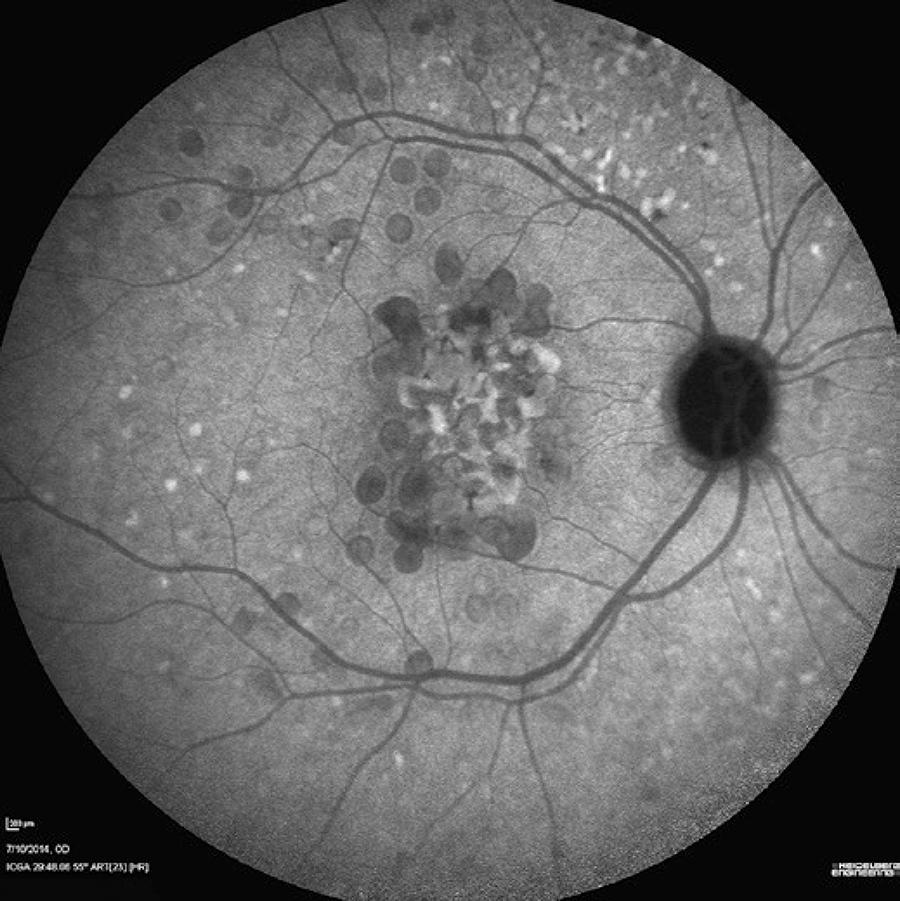

A 55-year-old Caucasian woman from São Paulo, Brazil, presented with the chief complaint of a 5-year history of progressively worsening vision, particularly in the left eye. She had a 70-pack/year smoking history and a diagnosis of emphysema. She had not had any previous ocular surgeries, and there was no history of other familial diseases. Her best-corrected visual acuity levels were 20/40 in the right eye and 20/400 in the left eye. The pupillary reflexes were preserved and the anterior segment was normal. Indirect ophthalmoscopy revealed large sub-retinal yellowish lesions in the macular area and the mid periphery of the retina bilaterally. Fluorescein angiography showed early hyperfluorescence; ICGA showed that most drusen appeared hypofluorescent. En face OCT showed a hyper-reflective center surrounded by a hypo-reflective halo, which was bordered by hyper-reflective and hypo-reflective rings. In OCT B-scans, all drusen appeared convex with medium and homogenous internal reflectivity, marked attenuation of the ellipsoid zone overlaying the LCD, and RPE atrophy. Posterior segment findings can be seen in figure 1, while figure 2-4 display image findings. A conservative approach was adopted, and the patient was instructed to quit smoking and perform the Amsler Grid test routinely.

Figure 2 Optical coherence tomography (OCT) images obtained from a 55-year-old woman with large colloid drusen (LCD). A) Structural en face OCT with upper segmentation line located at the avascular outer retina and lower segmentation line placed at the sub-retinal pigment epithelium (RPE) space showing a hyper-reflective center surrounded by a hypo-reflective halo, bordered by hyper-reflective and hypo-reflective rings, similar to the donut effect. B) Corresponding OCT B-scan of (A) showing the convex contour of LCD with medium and homogeneous internal reflectivity under the RPE, as well as marked thinning of the outer nuclear and ellipsoid layers. A small area of RPE atrophy as seen under the horizontal foveal scan, identified as reverse shadowing (black arrow). No fluid accumulation is observed. C) Structural en face OCT on a choroid slab showing a hyper-reflective center surrounded by a hypo-reflective halo. D) Choroidal features on the OCT B-scan were not well defined due to signal blockage caused by the colloid drusen.

The images obtained from this patient showed features of LCD. In the late-phase ICGA images, the larger drusen appeared hyperfluorescent with a hypofluorescent halo, traditionally described as the donut effect(3) (Figure 3). Drusen are lipid-rich, and the relative hydrophobicity of the commonly used angiographic dyes differs. A difference in the lipid composition between the core and the periphery of LCD has been reported, which might be responsible for the typical donut shape observed in the ICGA images(1).

The structural en face OCT images showed a hyper-reflective center surrounded by a hypo-reflective halo bordered by two rings, one of which was hyper-reflective and the other hypo-reflective, similar to the donut effect seen on the ICGA images (Figure 2). OCT is noninvasive and can help differentiate LCD from other early-onset drusen, such as Malattia Leventinese and cuticular drusen. In OCT images, LCD have been described as having a sawtooth pattern, with the height of each LCD approximately equal to its basal diameter. The neurosensory retina appears to be spared in the area overlaying the drusen, although the overlaying RPE is much thinner at the apex of each druse than between the drusen. In Malattia Leventinese, confluent sub-RPE accumulation on OCT has been reported. The smaller drusen of this condition have a radial distribution and a confluence of large drusen with sub-retinal fibrous plaque occurs. The typically pale drusen are adjacent to the optic disc(3). Furthermore, OCT allows observation of focal loss of cellular visibility, which has a mosaic pattern in patients presenting with drusen(6,7). The smallest LCD do not affect the ellipsoid zone(5). This imaging approach might serve as the foundation for valuable imaging-based biomarkers for detecting the earliest disease stages, tracking progression, and monitoring treatment response(9).